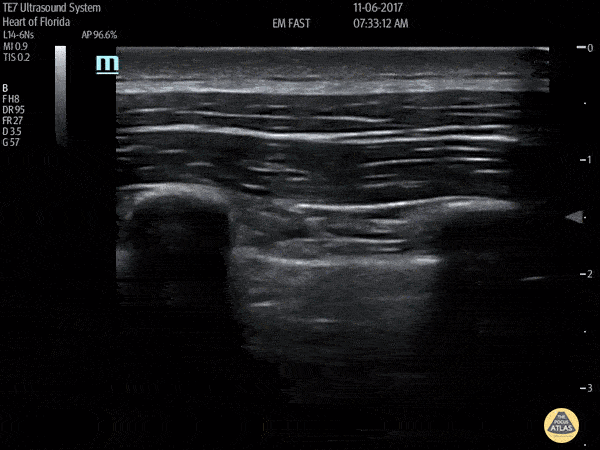

🌪️ Pneumothorax

L’air sépare la plèvre viscérale de la pariétale.

Signes échographiques

- Absence de glissement pleural : ligne pleurale statique.

- Absence de lignes B, lignes A prédominantes.

- Mode M : « signe du code barre » (lignes horizontales parallèles au-dessus et au-dessous de la plèvre, sans granulation).

- Point poumon : zone de transition entre glissement présent et absent → signe spécifique de pneumothorax.

Explorer en priorité les régions antérieures et supérieures, car l’air remonte → Chez un patient allongé, commencer par les zones antérieures.